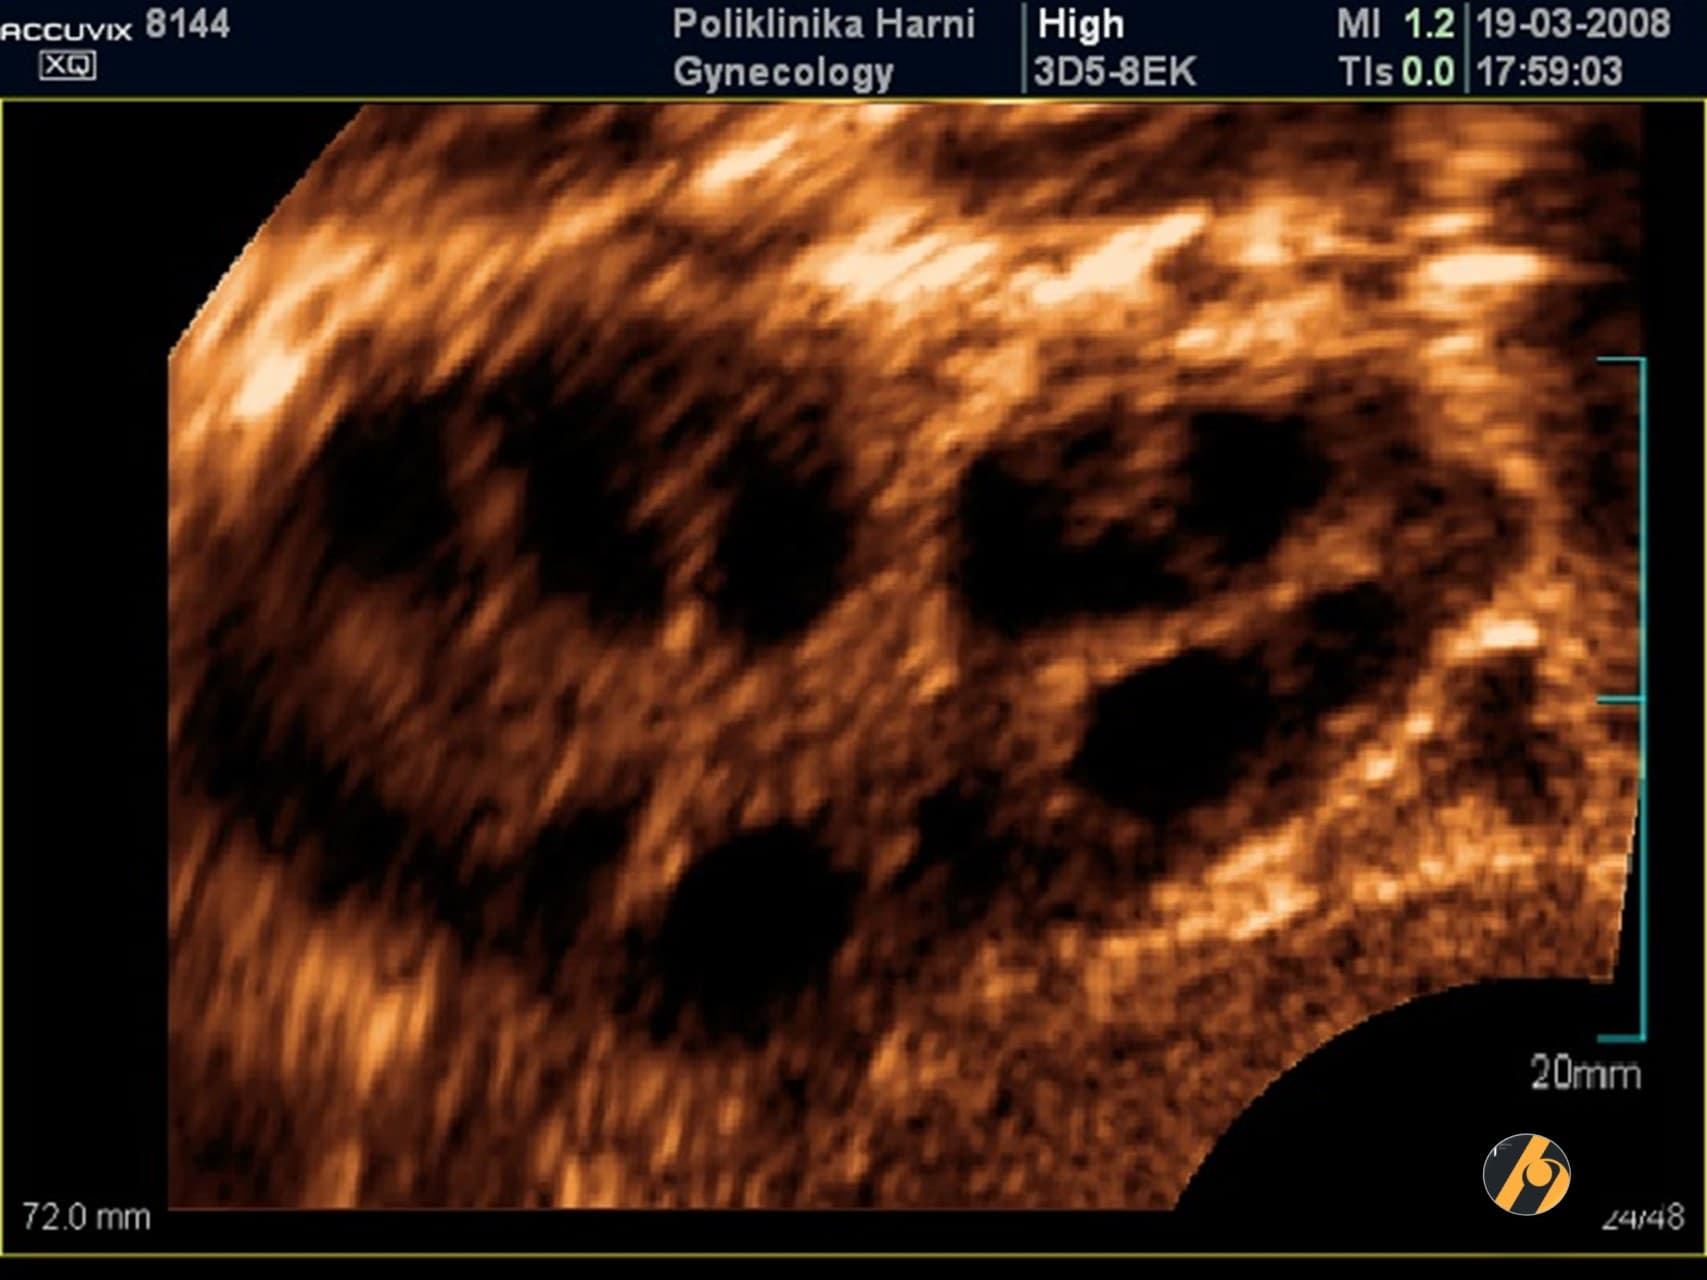

Premda su kardinalna obilježja ovog sindroma hiperandrogenizam i policističan izgled jajnika, niti jedan od pojedinačnih kriterija nije dovoljan da bi se postavila dijagnoza sindroma policističnih jajnika. Osnovna metoda u dijagnostici PCOS je ultrazvučni pregled. Koristi se transvaginalni ultrazvuk, prilikom čega se procjenjuje jesu li povećani jajnici, je li stroma - unutarnji dio jajnika koji proizvodi hormone, zadebljana, postoje li veliki broj folikula koji često tvore sliku ogrlice od perli ako su smješteni periferno ili stvaraju dojam mikrocističnosti kod difuznog rasporeda.

Dijagnoza PCOS prema Rotterdamskim kriterijima postavlja se kada žena ima najmanje dvije od sljedeće tri manifestacije: neredoviti menstrualni ciklusi ili anovulacija, povišena razina muških spolnih hormona i/ili jajnici čiji je volumen veći od 10 ml s najmanje 12 folikula na jednoj zamrznutom ultrazvučnoj slici jajnika. Nužno je isključiti ostala stanja sa sličnim znacima kao što su tumori koji stvaraju muške spolne hormone ili Cushingova bolest. Jajnici koji imaju policističan izgleda, s normalnom funkcijom i bez povišene razine muških spolnih hormona ne spadaju u sindrom policističnih jajnika i ne treba ih kao takve liječiti.

Uz ultrazvuk se u postavljanju dijagnoze PCOS koristi i niz drugih pretraga kao što su mjerenje protoka krvi kroz jajnike (kolor Dopler), određivanje bazalnog hormonskog statusauz analizu metabolizma – određivanje inzulinske rezistencije praćenjem razine glukoze i inzulina i testa opterećenja šećerom - OGTT, analiza učinkovitosti inzulina, mjerenje količine i rasporeda masnog tkiva i druge pretrage, ovisno o vodećim simptomima.